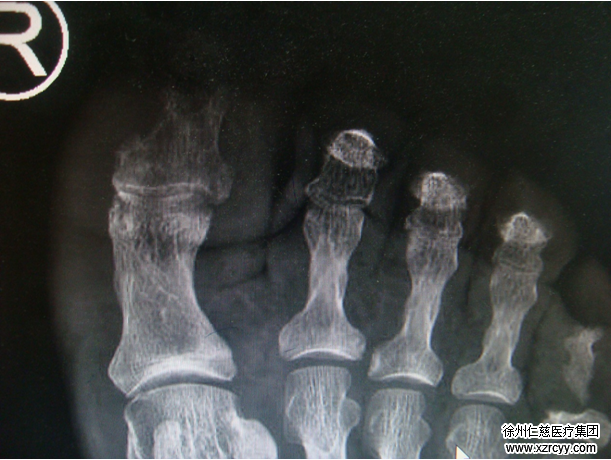

李大伯的主治医生,betway在线登陆慢创中心主任刘衍松介绍“这个病人,是典型的糖尿病足。这是一种最常见的糖尿病严重并发症之一。好发于糖尿病史超过5年,又控制不好血糖的患者。”指着伤口,刘主任继续说“糖尿病患者如果长期血糖控制不佳,周围血管或神经发生病变,就容易患上糖尿病足病。”

经过与家属的沟通,针对李大爷的病情,刘衍松主任为其制定了治疗方案:术中给以清创去除了坏死感染的组织——伤口彻底清洗、引流——伤口清洁后二次手术闭合创面——伤口进行积极换药治疗——保持足部干燥。

糖尿病足反映了糖尿病造成足部神经、大血管的病变,并导致局部组织的破溃、感染、骨髓炎、坏死等,可并发或诱发其他急性心脑血管事件,甚至诱发糖尿病急性并发症,如酮症酸中毒、高渗透压综合征。